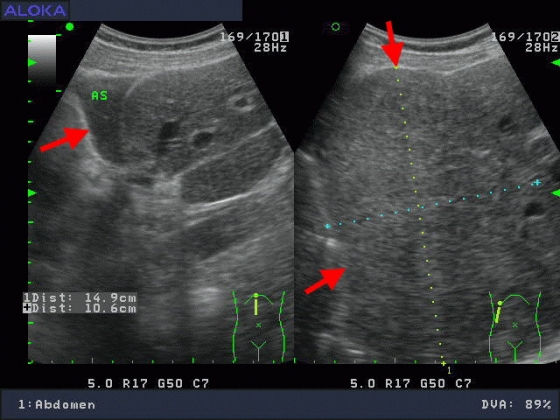

肝癌

醫學影像..腹部超音波 :肝臟